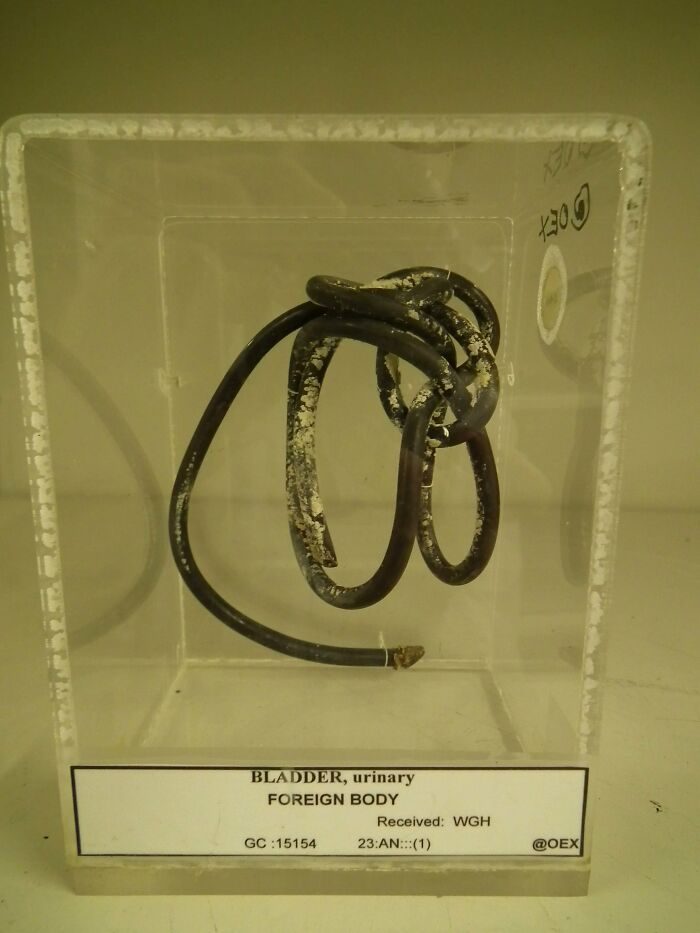

Coax Cable Removed From A Man's Bladder. "It Had Become Encrusted With Phosphate And Had Coiled To The Anatomical Curves Of The Bladder." Only One Way It Got Up There